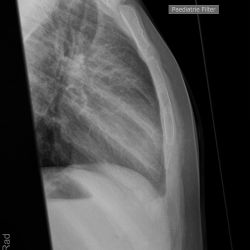

Wulstfraktur des Manubrium sterni